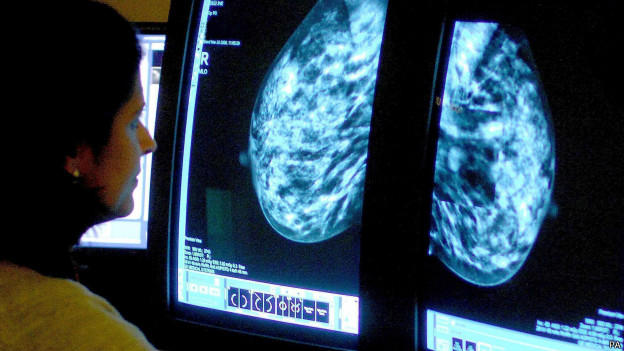

اكتشاف عقاقير جديدة لعلاج أمراض سرطان الثدي المستعصية.

يقول علماء إن البحوث الخاصة بمرض سرطان الدم (اللوكيميا) قد تقود إلى اكتشاف عقاقير جديدة لعلاج أمراض سرطان الثدي المستعصية.